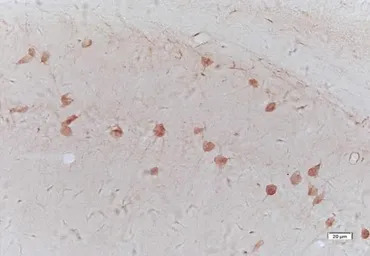

IHC-P analysis of rat spinal cord tissue using GTX37691 Galanin antibody.

IHC-Fr analysis of mouse brain tissue using GTX37691 Galanin antibody.